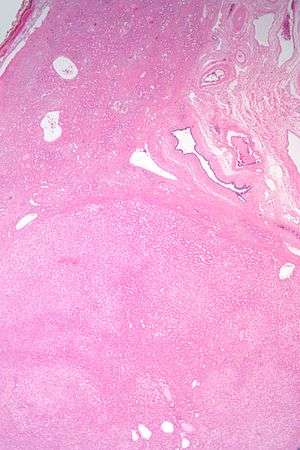

| Micrograph of a hepatic adenoma (bottom of image). H&E stain | |

Hepatic adenomas are, typically, well-circumscribed nodules that consist of sheets of hepatocytes with a bubbly vacuolated cytoplasm. The hepatocytes are on a regular reticulin scaffold and less or equal to three cell thick.

The histologic diagnosis of hepatic adenomas can be aided by reticulin staining. In hepatic adenomas, the reticulin scaffold is preserved and hepatocytes do not form layers of four or more hepatocytes, as is seen in hepatocellular carcinoma.

Cells resemble normal hepatocytes and are traversed by blood vessels but lack portal tracts or central veins.